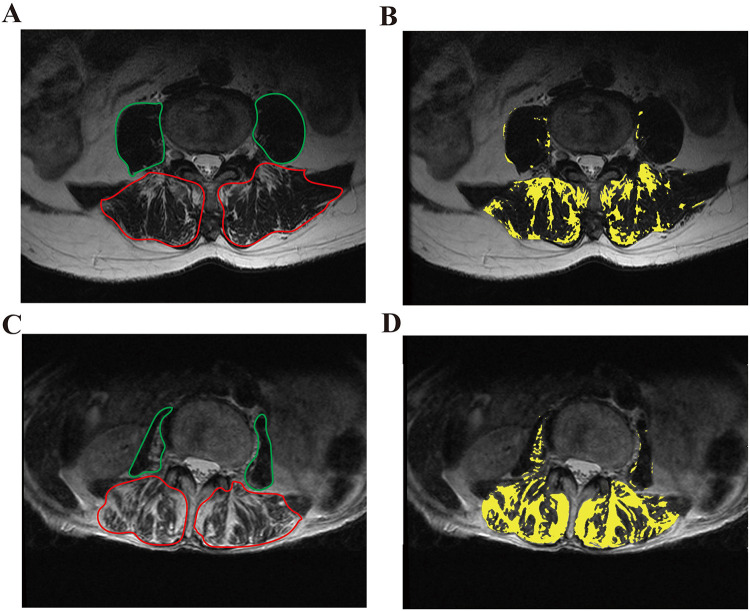

Methods: This retrospective cohort study included 213 patients (mean age 70.88 ± 8.58 years; 82.2% female) with single-level OVFs who underwent PKP between January 2021 and June 2023. Patients with multiple-level fractures, chronic LBP, neurological deficits, prior spinal surgery, incomplete imaging, or inadequate follow-up were excluded. Fat infiltration percentage (FI%) and cross-sectional area of the multifidus (MF), erector spinae (ES), and psoas major (PS) were measured at the L4 level using transverse T2-weighted MRI. Residual LBP was defined as postoperative VAS ≥3.5 at 12-month follow-up. Logistic regression and ROC analyses were conducted and appropriate univariate tests (t-test or Mann-Whitney U-test) were performed.

Abstract Image